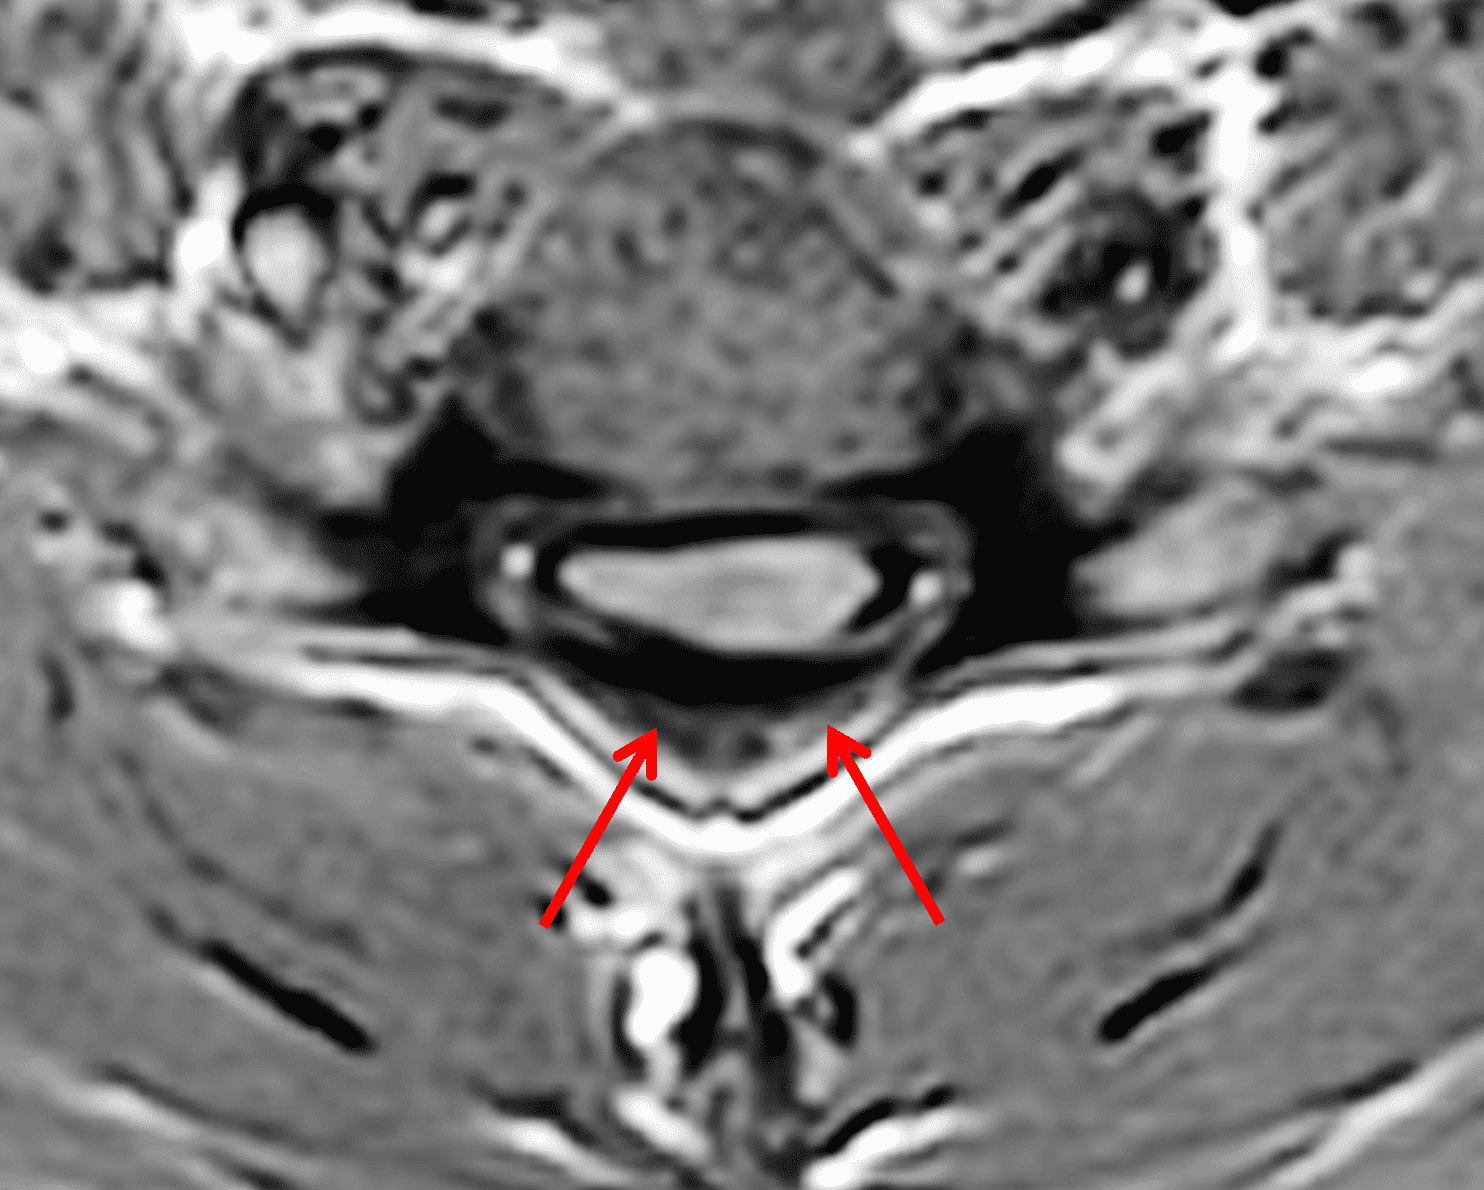

Figure 2: Neutral images of the cervical spine. Sagittal (2A) T2-weighted, (2B) T1-weighted, and (2C) STIR images show mild kyphosis, an enlarged posterior epidural space with loss of attachment of the dura (red arrows), and cord atrophy at the C6 level (yellow arrow). Subtle cord hyperintensity on the water sensitive images at the C7 level (green arrows) likely represents gliosis. (2D) Axial T2-weighted image shows enlargement of the posterior epidural space, right greater than left (red arrows). (2E) Axial T1-weighted image shows an enlarged posterior epidural space (red arrows) and cord atrophy, more severe on the right (yellow arrow).

The LOA sign was proposed as a finding suggesting HD on neutral position MRI of the cervical spine.29 The degree of loss of attachment of the posterior dural sac and subjacent lamina are evaluated on each side of the lamina at C4 to C6 levels on axial T2-weighted images, with separation along more than one-third of the lamina on one or both sides considered positive for LOA. To assess the degree of LOA, the lamina is defined medially by the point of junction of the lamina and laterally by a tangential line along the medial aspect of the pedicle and then divided into three equal parts (Figure 6). The LOA sign was found to have a sensitivity of 93.5% and specificity of 98% for HD. The LOA sign was investigated in the first multisite North American study by Lehman et al.5 and found to have a lower sensitivity of 70% but similar specificity of 100%. The authors confirmed that the LOA sign and other findings are often present on neutral position MRI and in the appropriate clinical scenario, should raise suspicion and prompt further assessment by flexion MRI to confirm the diagnosis.

Figure 6: Axial images demonstrating the loss of attachment (LOA) sign. (6A) T2-weighted and (6B) T1-weighted images in a normal spine (same patient as Figure 3). Yellow lines mark the lateral extent of the laminae, which have been divided into thirds (yellow dots). The posterior dura (red arrows) is firmly attached to the lamina. (6C) T2-weighted and (6D) T1-weighted images of a spine with HD (same patient as Figure 1) show the lamina divided into three equal parts (yellow lines and dots) and displacement of the posterior dural sac, right greater than left, with loss of attachment (red arrows). The separation involves more than one-third of the length of the lamina on both sides.